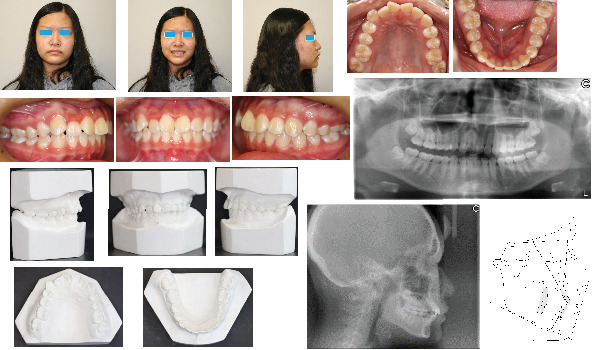

Background: Treatment of Class II subdivision can present a challenge for the clinician because of its asymmetry and possible midline deviation. This case report documents the use of a computer-aided design/computer-aided manufacturing (CAD/CAM) surgical guide for miniscrew placement in a Class II subdivision treatment. Case Presentation: A 17-year and 1-month-old female presented with a skeletal Class I relationship, but mild mandibular skeletal and dental midline shift to the right relative to the facial midline. A full-step Class II molar relationship on the right side and slight Class III molar relationship on the left side and a 4.0 mm deficiency of space in the maxillary were noticed. Using CAD/CAM technology, a surgical guide was designed virtually and 3D printed for predrilling. With the surgical guide, one ø1.3 mm twist drill was chosen to prepare a 4-5 mm deep hole in the alveolar process distobuccal to the maxillary right second premolar. A ø1.4 mm × 8.0 mm miniscrew was inserted into the prepared hole. With this miniscrew, the unilateral Class II relationship was corrected successfully by distalization of the unilateral maxillary dentition on the Class II side after 13 months of treatment. Conclusion: Application of CAD/CAM surgical guide is very helpful for placement of the miniscrew. Class II subdivision may be treated by distalizing unilateral maxillary dentition on the Class II side using the miniscrew.